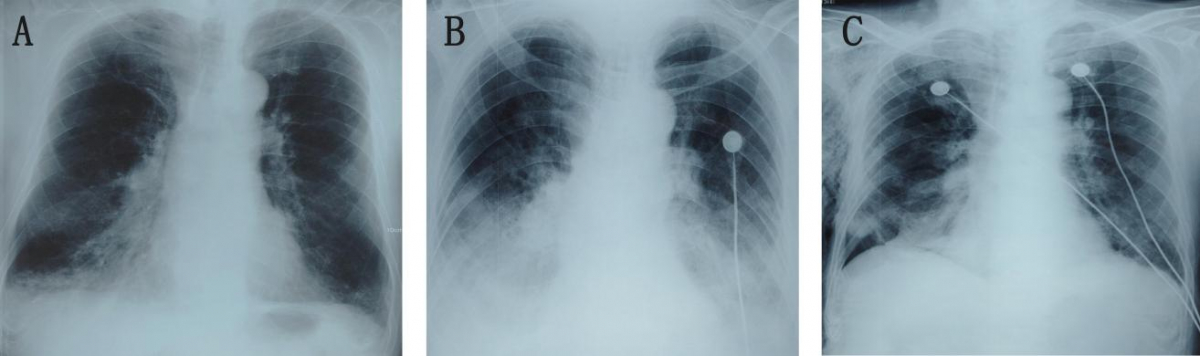

心衰型COPD-IPA的胸部X线表现

图像来自一位82岁男性COPD患者,因“咳嗽、咳痰、气短加重7天”入院。住院期间患者出现进行性加重的呼吸困难、端坐呼吸及痰中带血。(A)症状出现前的胸部X线显示双下肺野斑片状影,肺门边界清晰。(B)症状出现后的胸部X线显示双下肺阴影范围较前片增大,肺门显示不清,伴双侧新发胸腔积液。(C)抗真菌治疗4周后,肺部病变较前片明显改善。